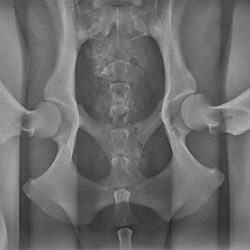

PennHIP Radiographs

Sedation, PennHIP views (3), submission & interpretation